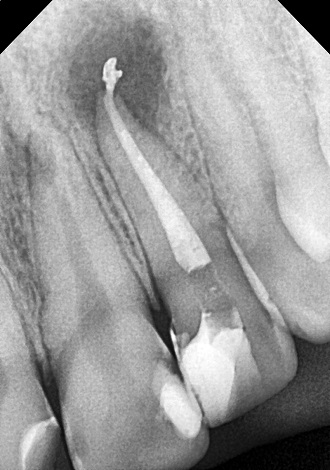

5. визначити глибину каналів зубного кореня;

6. механічна розробка каналів;

7. хімічна обробка каналів;

8. герметична обтурація.

Якісно запломбовані кореневі канали є основою довговічності. Тому очищення і пломбування кореневих каналів в «Домі Стоматології» приділяється особлива увага! Після пломбування кореневих каналів проводиться контроль якості пломбування за допомогою знімка.